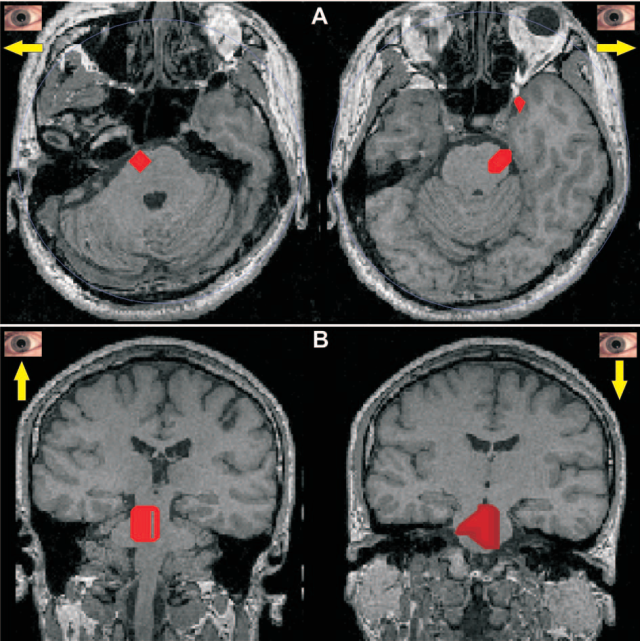

The MEG signals were recorded from three subjects while they performed a simple cued eye movement task.

Statistical parametric maps (SPMs) showing common activations in the brainstem for the 100 ms period just before saccades. In each case the SPMs were computed for each subject separately by comparing the moduli of the current density in the 100 ms leading to the saccade with the corresponding distributions in the far pre-stimulus period (-900 to -600 ms). The results were then transformed to the Talairach space and common activations across subjects identified for each voxel. The results were then backtransformed to the MRI of one of the subjects for display. (A) Shows the SPMs for horizontal eye movements (move left on left and move right on right) and (B) shows the SPMs for vertical eye movement (move up on left and move down on right). The red area corresponds to voxels of common statistically significant increase (P < 0.05) for all three subjects in the first three directions, but for only two subjects in down, possibly because for down, the subject produced fewer saccades satisfying the selection criteria.

The results of this study demonstrate that activity in the pontine gaze centers can be imaged millisecond by millisecond. The estimated activity pattern in brainstem was consistent with the known anatomy and functional organization of gaze centers. Taken together these results demonstrate the feasibility of accurate imaging of brainstem centers in both the awake state and during sleep. They therefore extend to the level of the brainstem the claim for accurate localization using post-MFT statistical analysis of non-invasive MEG signals.

A. A. Ioannides et al., Cereb. Cortex 14, 56-72 (2004). PDF >>